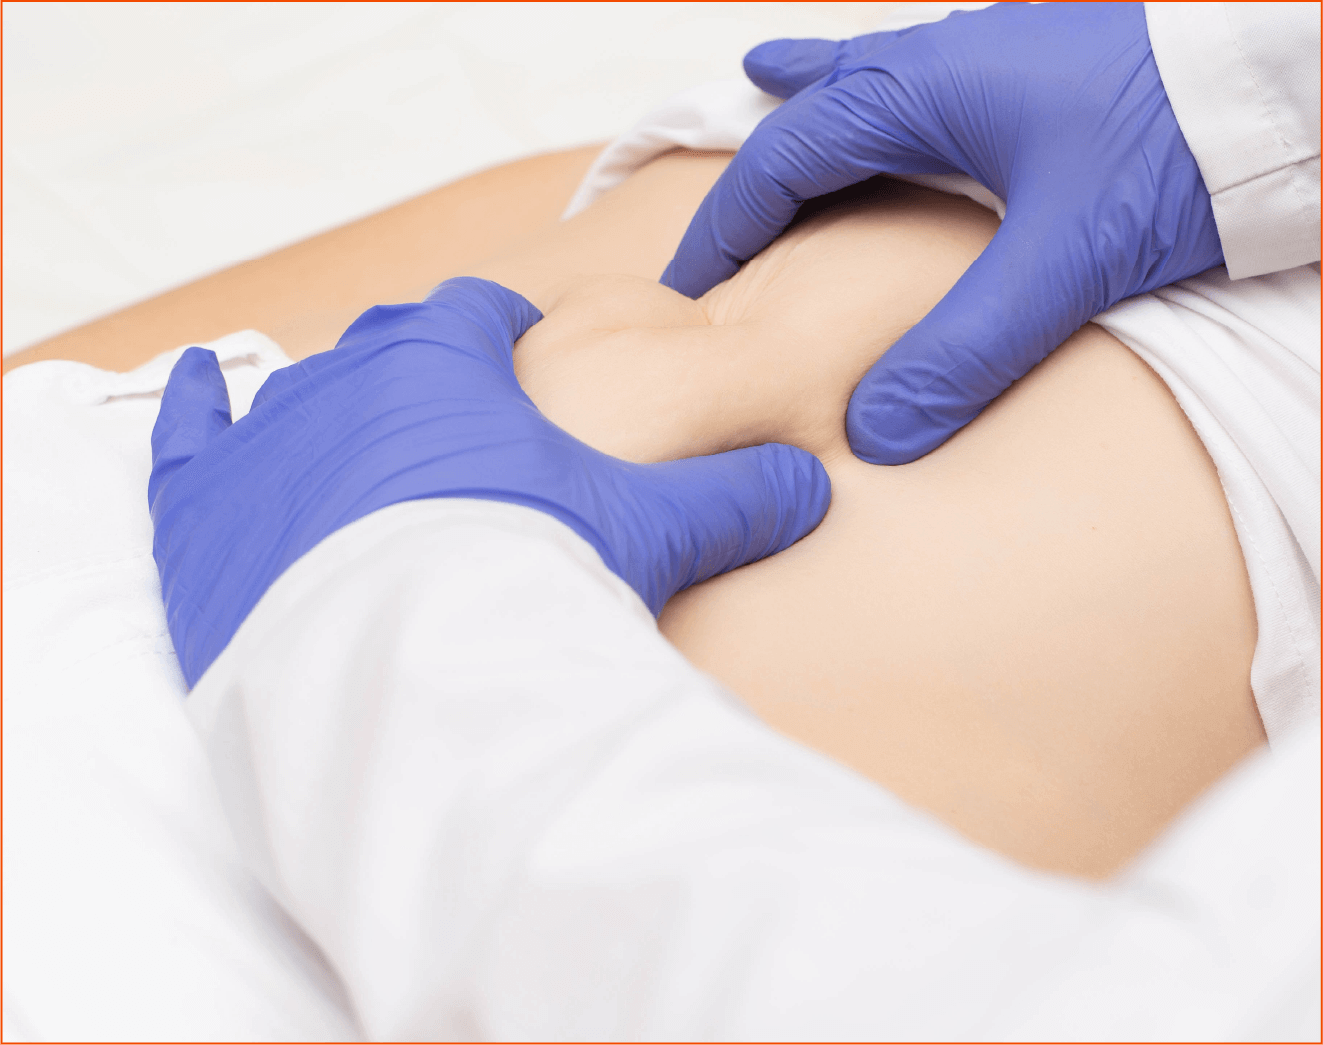

For many patients, parastomal hernias are asymptomatic and can be managed without intrusive measures, but some patients suffer significant morbidity and require emergency hernia repair. The impacts on patients can include pain, stoma leakage and skin excoriation. In more extreme cases, the bowel can be incarcerated, obstructed or strangulated.1

SMART creates a reinforced stoma trephine using a purpose-designed circular stapling gun of various diameters. The stapling gun creates a precise trephine and simultaneously fixes a mesh sub-peritoneally and circumferentially.8

Dynamesh provides anatomically correct mesh for any mesh insertion, but due to its specialist features, the ISPT can be especially useful in the repair of parastomal hernias.

The ISPT implant is made from a single piece of mesh for a seamless junction with the elastic panel. The three-dimensional pre-shaped implant provides excellent elasticity and flexibility to facilitate improved stomaplasty preparation for surgeons.

The dual-layer composite structure promotes rapid ingrowth into the abdominal wall whilst reducing the risks of adhesions on the visceral side.

The elastic funnel is free of sharp selvedges, leading to secure integration of the terminal segment of the bowel and prevention of parastomal herniation.

The ISPT-R can be placed without detaching the stoma from the stoma wall, as the prefabricated slit makes it easier to place the mesh implant around the terminal section of the bowel.